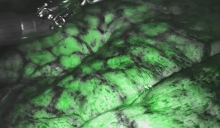

The authors then proceeded to the perfusion assessment. The da Vinci Firefly system involves the injection of indocyanine green (ICG) tracer into the blood, which is then detected using near-infrared imaging. Dilute 1 ampoule (25 mg) of Verdye (ICG) with 10 ml water for injection to give a 2.5 mg/ml solution. Administer the ICG in a 3 ml bolus and repeat as necessary, to an upper limit of 0.3 mg/kg. ICG is confined to the vascular system, has a half-life of 3-4 minutes, and is eliminated by the liver (1). The system allows for real-time intraoperative assessment of pulmonary perfusion, with ICG detectable in the lung parenchyma within seconds following injection, thus guiding resection. In this patient, the lingua demonstrated comparatively good perfusion, and therefore the targeted resection avoided this area entirely.